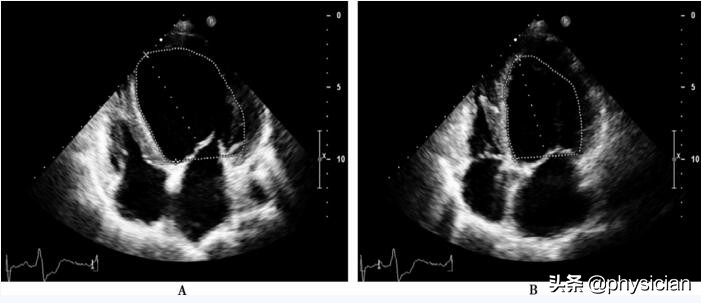

4,心血管磁共振、负荷超声心动图、核磁成像可以发现异常。

2,负荷超声心动图。,